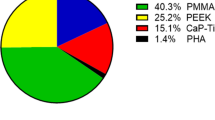

No consensus has yet been established in relation to the optimal material used [12]. Options consist of re-implantation of the autologous bone flap following freezing or subcutaneous preservation, or the use of an alloplastic material. The ideal material for cranioplasty should be biocompatible, radiolucent, non-magnetic, resistant to infections, a non-conductor of heat or cold, porous, malleable, durable, mechanical resistant, readily available, easy to use and low cost [46]. Commonly used commercially available allografts include polymethylmethacrylate (PMMA), titanium, polyetheretherketone (PEEK) and hydroxyapatite (HA).

Despite long-lasting debate, no consensus has been reported regarding the best cranioplasty material for cranioplasty [12, 33]. The results of published meta-analyses are controversial, and the strength of the analyses was additionally limited by the low quality and heterogeneity of the literature [3, 9, 12, 21, 23, 27, 40, 45]. Some meta-analyses have demonstrated the convincing inferiority of autologous bone. Others have shown that autologous bone can still be the first choice in patients with a low risk of resorption or for whom resorption might not be of major concern [3, 9, 21, 23, 40]. Aseptic bone flap resorption is unique to autologous bone and is the reason for a significantly higher removal rate and probably the decline in autologous cranioplasty. Discontinuance of institutional tissue banking due to increasing storage costs or national regulation with strict mandated biobanking requirements may also be reasons for switching to alloplastic materials in some countries [20, 37, 40, 46]. Moreover, the choice of material is not only addressed from the point of view of the incidence of surgical complications, but also from the health-economic perspective and established practices in different countries. As reported by Morselli et al., titanium is mostly used in Australia, the United Kingdom and Germany, PMMA in the USA, PEEK in the USA, Singapore and South Korea and HA in France and Italy [27].

The price of polyethylene is acceptable. With the exception of PMMA, the price of PE is the lowest among the alloplastic materials used for PSI (Titan, PEEK, HA) [40].